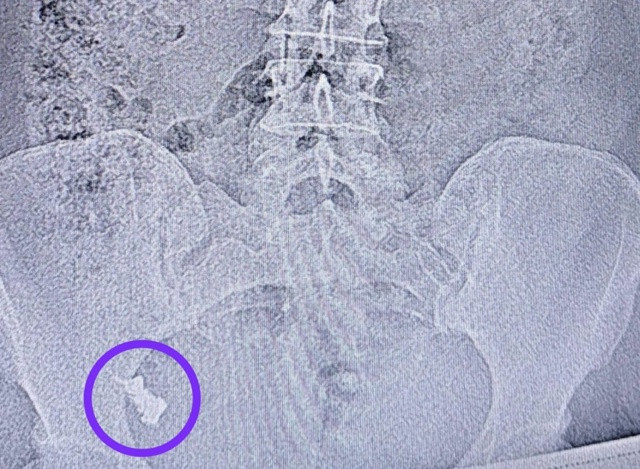

В Краснодарском крае 50-летний турист почувствовал себя плохо во время восхождения в горы на высоту в 1800 метров, ему на помощь был отправлен вертолёт Ка-32 со спасателями. Мужчина пожаловался на боли в сердце, было подозрение на инфаркт.

50-летнего мужчину доставили в Сочи из пастушьих балаганов Черкесского перевала. На борту воздушного судна туристу оказали доврачебную помощь. А после посадки вертолёта пациента сразу же передали врачам скорой помощи.